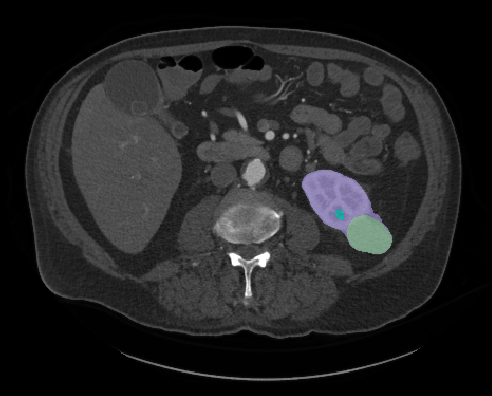

In 2019, Heller’s team organized a competition and released their vast data collection on kidney tumors to the public. Known as the Medical Image Computing and Computer-Assisted Intervention (MICCAI) Kidney Tumor Segmentation Challenge, or “KiTS,” Heller asked participants to design and train their own machine learning algorithm models using the data and parameters given to them. As it turns out, the UMN group’s segmented kidney cancer dataset was the first of its kind to be used in this type of competition—and drew a lot of interest in the medical community. “We had more than 100 teams from around the world participate in the challenge,” he says. “The event was held in conjunction with a conference in China, so there was a lot of international collaboration. It was a great experience.”

As the lead organizer, Heller and his team evaluated each entry, ranked them from most successful algorithmic designed model to least successful, and published the results on their website.

The KiTS Challenge was so popular, Heller’s group organized a second competition in 2021.